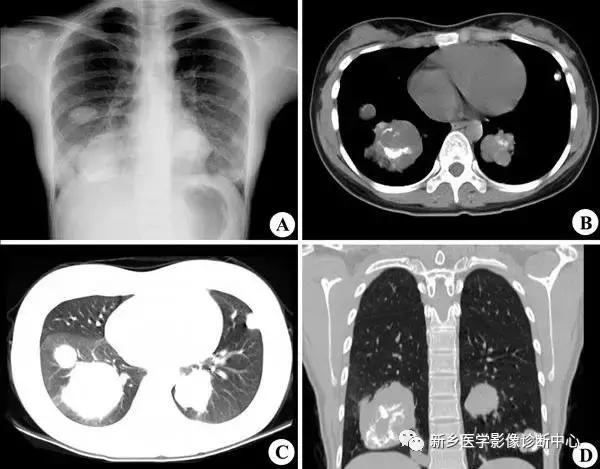

炎性假瘤

常有胸痛,咳嗽,发热,咳血。孤立类圆形肿块,密度均匀,边界清楚,少数可有斑点样钙化,抗炎治疗可缩小消失。

桃尖征,平直征: